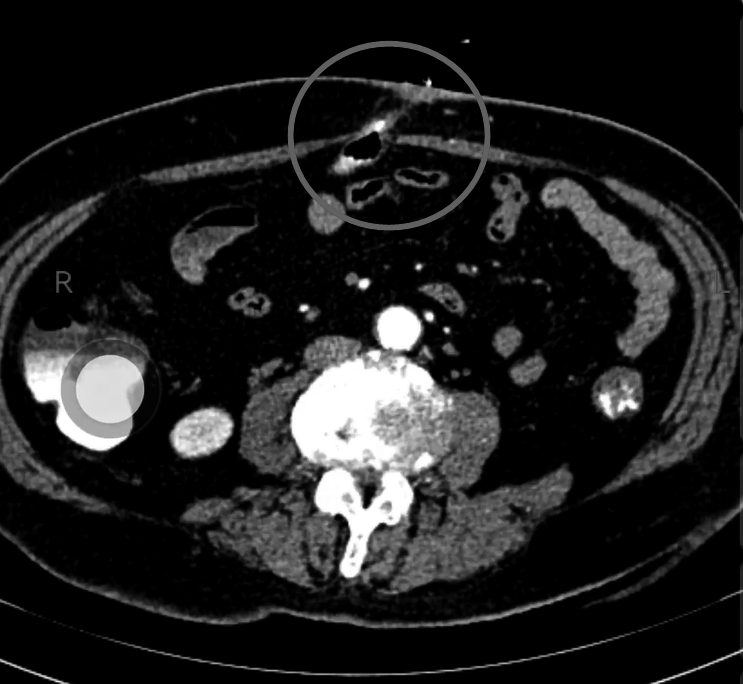

70多岁的王女士来到医院就诊,刚开口说话,立马脸就红了。她说肚脐发炎了,流出的东西跟大便一样,觉得很脏,一直羞于看医生,最近感觉症状越来越严重,还出现了肚子痛,这才来到医院就诊。 通过检查,我发现王女士的肚脐上有一个洞,周围红肿,一碰就痛;挤压肚脐,周围会流出像大便一样的东西。我拿着棉签探了探,发现里面很深,已经进入腹腔。 直觉告诉我,这不是单纯的脐炎,一定另有“玄机”。 通过进一步了解,我得知,几十年前,王女士这里曾经有一个包块,因为不痛不痒,包块也能下去,一直也没治疗;最近一段时间,这个包块变大了,变硬了,隐隐还出现了疼痛,并且破溃了,开始流出来的是带有臭味的脓液,换了几次药不见好转,最后流出来的就是像大便一样的东西。 多年的经验告诉我,这应该是一个特殊的脐疝——Richter疝(一种特殊的嵌顿疝),疝出来的只是一部分肠管,卡住之后出现慢性缺血和坏死,最后穿孔、破溃,导致大便从肚脐里流出来。王女士的CT检查结果证实了我的判断:横结肠的一部分肠壁从肚脐疝出来了,穿孔之后形成了肠瘘,因为大部分的肠管还是通畅的,所以并没有形成肠梗阻。王女士出现的疼痛,则是脐疝周围的感染引起的。 真相终于大白。接下来,我们为王女士实施了腹腔镜下的微创手术:切除了肠瘘,修补了脐疝。 术后没几天,王女士就康复了,很快出院。 我在这里提醒大家,Richter疝是一种特殊类型的疝,指的是肠壁的一部分进入疝囊,而肠系膜侧肠壁及系膜不进入疝囊,多由慢性腹腔压力增加而引起,较高的腹腔内压力使得腹膜被推挤进入人体先天性薄弱区域,从而形成疝囊。由于疝环狭小,疝囊浅,当肠管疝入时只有肠壁的一部分成为疝内容物,而肠系膜侧肠壁没有进入疝囊;同时,由于周围组织弹性差,肠壁一旦疝入很难自行复位,常常造成肠壁的嵌顿,使患者出现腹痛、呕吐等症状,严重时甚至出现坏死及穿孔。通过彩超或者CT检查往往可以明确诊断,而手术则是唯一可以治愈的方法。 (作者供职于郑州市中心医院)